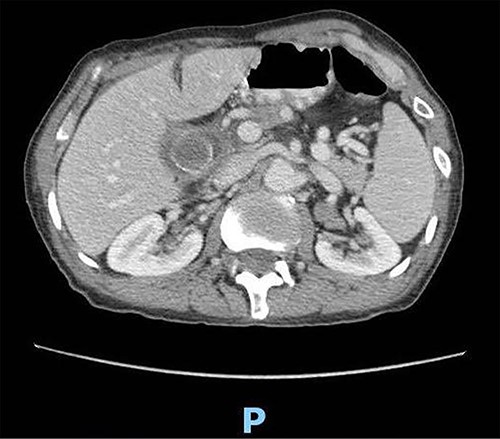

Upon clinical examination, the patient was vitally stable. Abdominal examination revealed a distended abdomen with generalized tenderness. Digital rectal examination revealed an empty rectum with no palpable masses. Laboratory investigations were unremarkable (Table 1). Abdominal X-ray was done (Fig. 2) and showed dilated large bowel loops suggestive of bowel obstruction. Enhanced CT scan of the abdomen and pelvis was obtained (Figs 3–5) and showed a dilated large bowel loop, with air fluid level. A 2.5-cm gallstone was noted, impacting the sigmoid colon and causing partial large bowel obstruction. There was evidence of pneumobilia with air foci within the gallbladder with a suspected fistula with the hepatic flexure.

Enhanced CT scan of the abdomen showing a gallbladder stone impacted at the sigmoid colon, with a significantly enlarged prostate causing narrowing of the rectosigmoid junction (axial view).